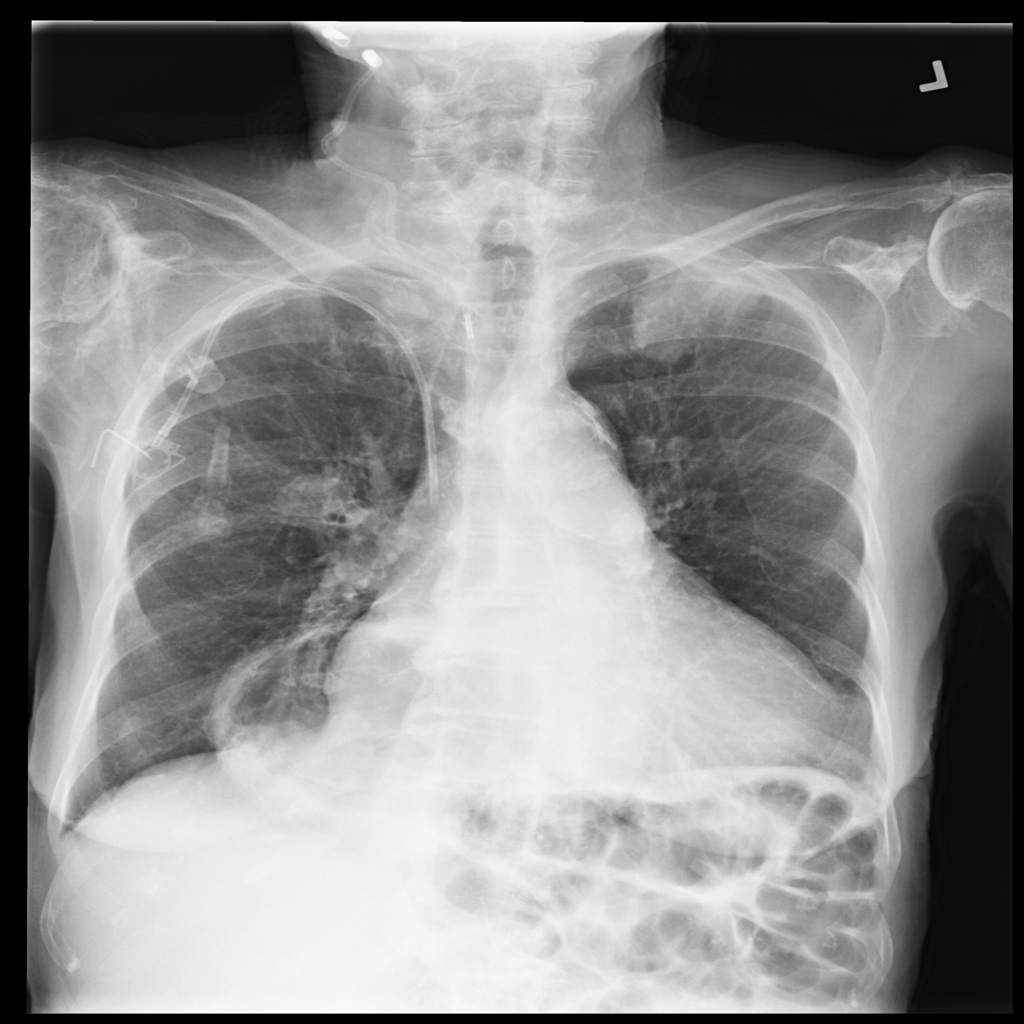

Showing up to 90 reference images for Hernia.

PAT-4F7E · IMG-000Hernia

PAT-4F7E · IMG-000

PA